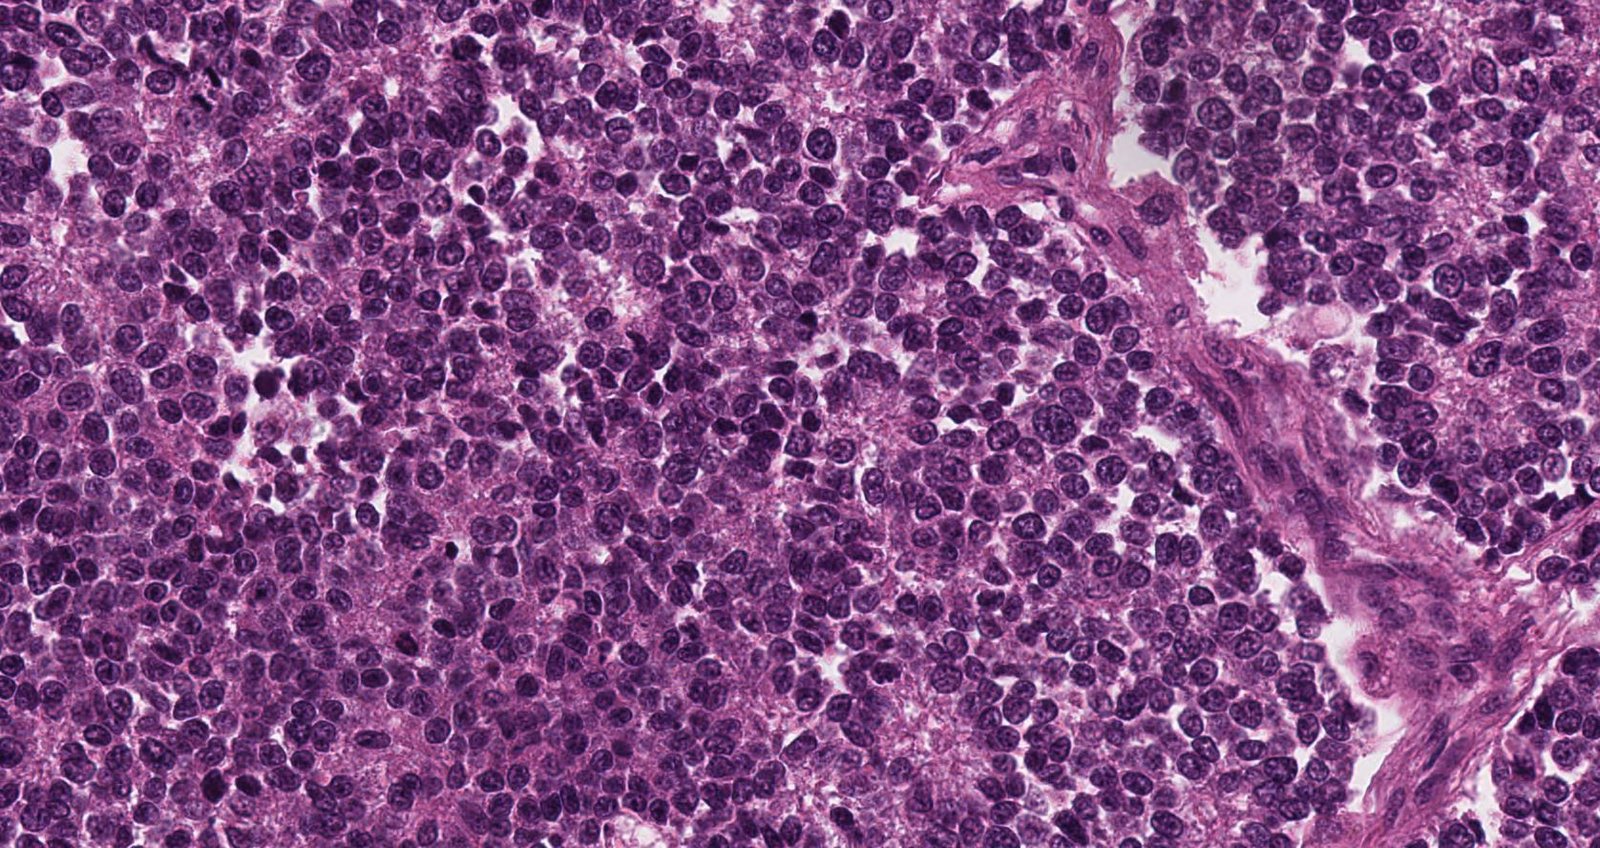

Case: TibialMass

Specials to Order:

Final Diagnosis: